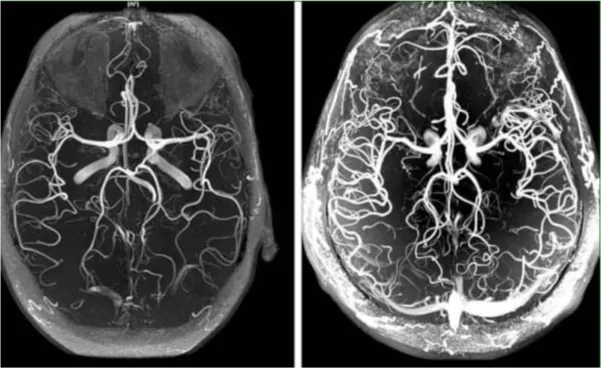

სპეციალურად ვიპოვე სურათი, რომელიც აღწერს ,თუ როგორ ვხედავდი საგნებს